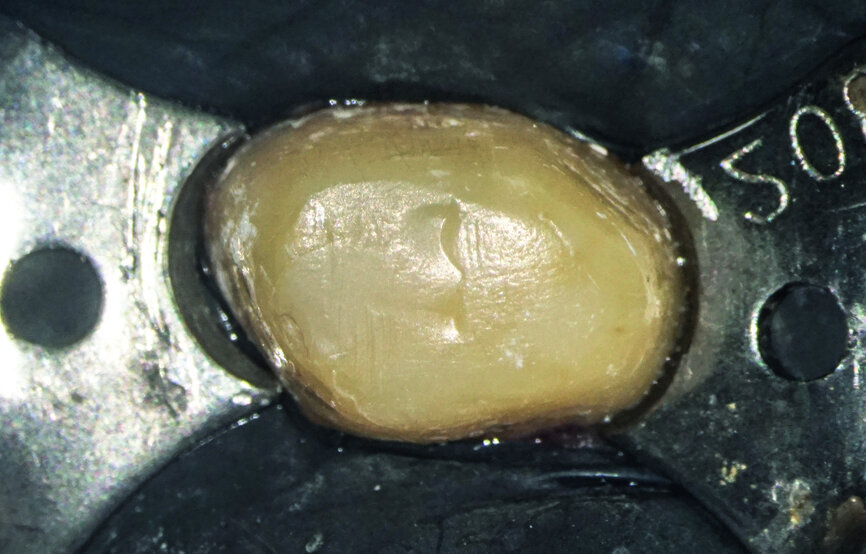

The patient who is the focus of our discussion came to our office reporting intense pain in response to hot and cold stimuli in the left maxilla (Fig. 1). He described the pain as being spontaneous at times and that in order for it to subside administration of anti-inflammatory medication was required. Upon examination, an accurate diagnosis was established of symptomatic irreversible pulpitis affecting tooth #27. The patient had had the tooth prepared for a crown sometime in the last 60 days (Fig. 2), but unfortunately the treatment was not completed for unknown reasons. Caries seemed to be absent; therefore, a minimally invasive approach was planned. Most likely, the pathology was caused by either trauma or an iatrogenic event.

After isolation of the tooth (Fig. 3), an access cavity was created using high-speed diamond burs and ultrasonic tips (Figs. 4–8). Pre-flaring in the coronal and middle thirds was done with the HyFlex EDM 25 instrument (at a torque of 4 Ncm and a speed of 500 rpm). It is a proven fact that pre-flaring allows an increase in the instrument size that binds in the root canal, irrespective of the discrepancy between the size of the file and anatomical diameter. [19–21] Afterwards, canal scouting was performed using an ISO size 10 stainless-steel K-file up to working length. Upon establishing the working length, with the help of an apex locator, the 10/05 EDM file (glide path file) was used up to working length (at a torque of 3 Ncm and a speed of 300 rpm). Subsequently before finishing the preparation with the 25 EDM file, the 20/05 EDM (preparation file) was used to full working length (at a torque of 3 Ncm and a speed of 400 rpm). At this point, the working length was confirmed again with an ISO size 20 NiTi K-file. Root canal shaping was completed with the 25 EDM file, which was inserted to full working length (at a torque of 3 Ncm and a speed of 400 rpm; Figs. 9–12).